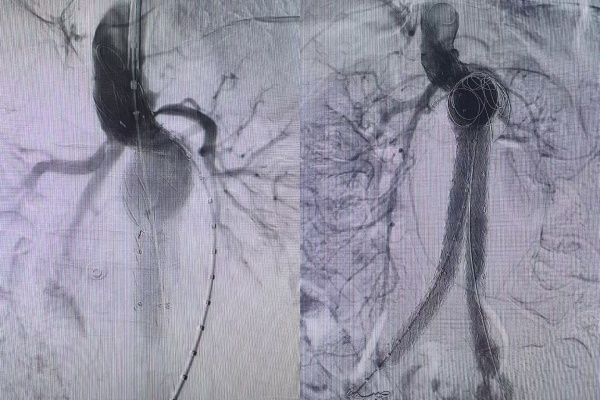

在血管外科马建仓主任的有力调度下,各专业各司其职,在最短的时间内完成必要的检查以及术前准备工作。虽然时值周末,但是患者的病情刻不容缓,血管外科团队在影像科的协助下顺利为患者实施了介入手术,运用娴熟的技术,为患者成功隔绝瘤体。在手术过程中,由于患者瘤体体积非常大、整体扭曲非常严重、瘤颈短非常严重、极限铆定、重重困难均在扎实的技术前被一一突破,支架置入完成后,通过造影确认完全隔绝无内漏发生。血管外科医护人员用 2 个小时紧张激烈的奋战,为患者成功排雷,术后 24 小时即下床活动,行动自如。